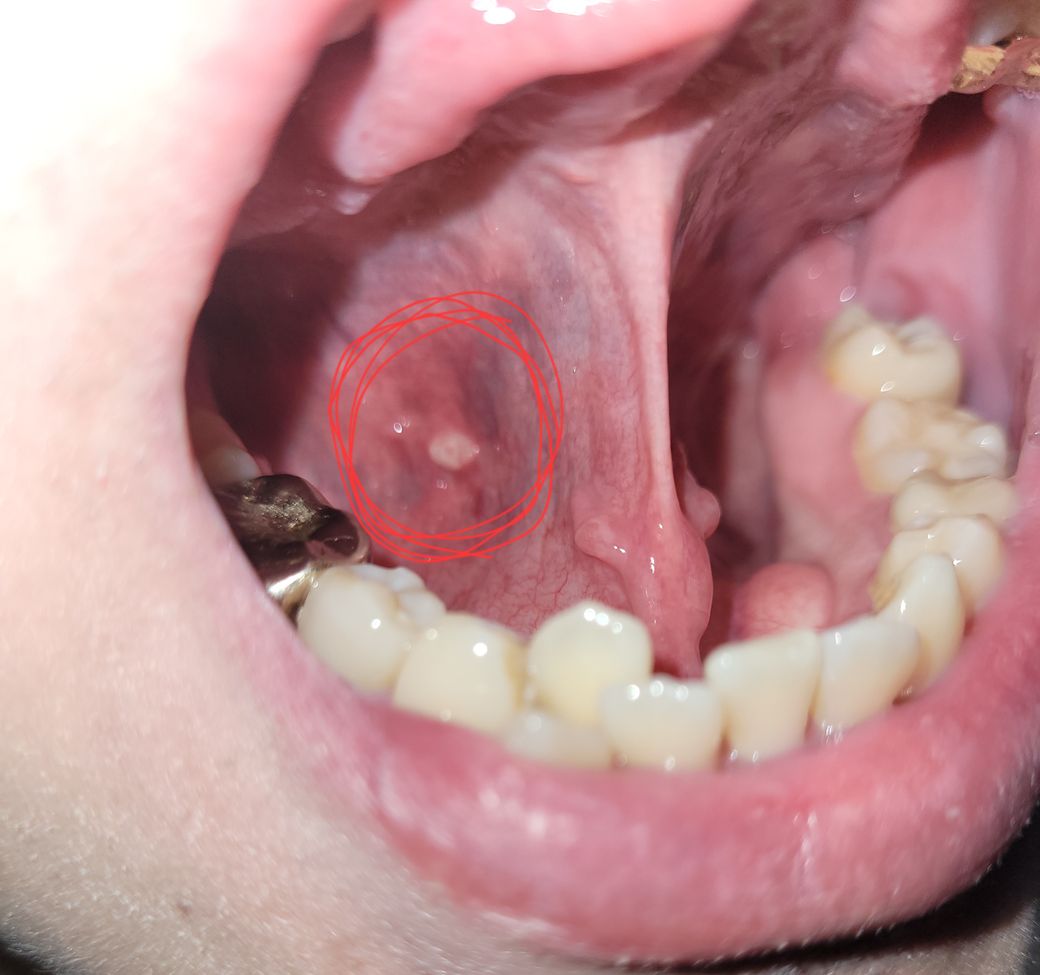

혀밑에 혹같은게생겼는데 뭘까요??

어제 혹같은게생겼는데 아프거나그러진 않습니다 혹시 이게 뭘까요? 아프거나 그러진않는데 혹이 만져지니 신경이쓰여 질문드립니다 ㅠㅠ

구강궤양으로 보입니다.

헤르페스바이러스에 의한 구강궤양으로 보여

알보칠등의 약을 사용하면 호전이 될것 같습니다.

다만 사진이라 명확치 않아 근처 의원 진료를 한번 보시면 좋겠습니다.

사진의 소견을 통해서 보았을 때에는 생긴 모양이 혹이라기 보다는 궤양성 병변에 가깝습니다. 즉, 구내염이 발생하였을 때 보이는 소견인 것 같습니다. 관련하여서는 정확한 감별 진단을 위해서 이비인후과 진료 및 검진을 받아보시길 권고드립니다.